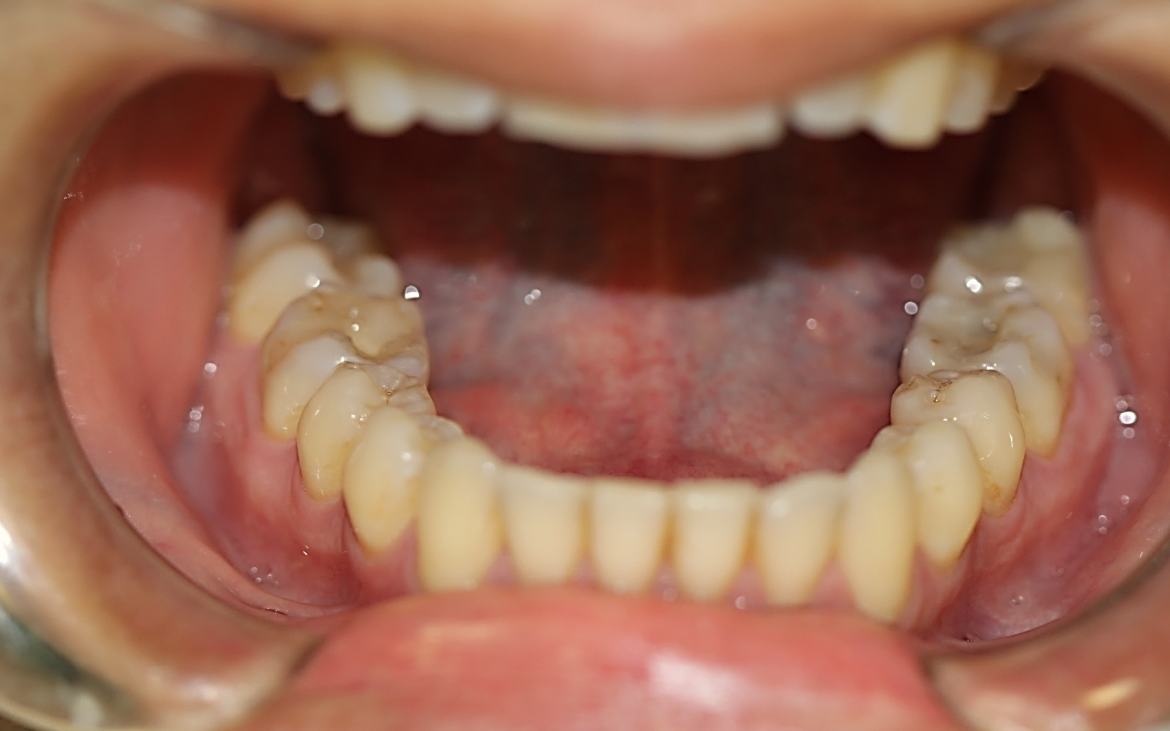

4- Vista oclusal dos dentes inferiores (Cor A3)

Restaurações inlays de compósitos nos dentes 36, 37 e 46.clinicamente satisfatórias.

demais elementos com esmalte hígidos